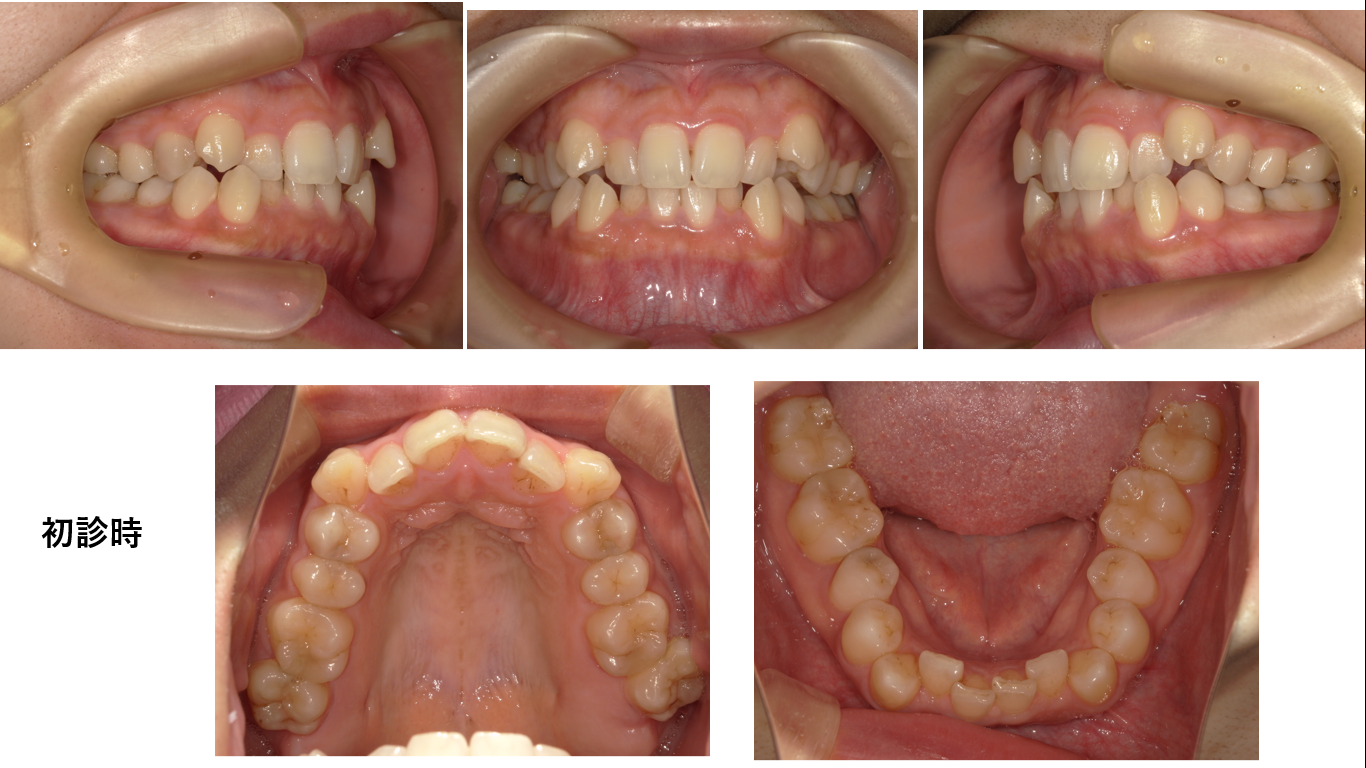

矯正症例 140 AngleⅠ級上下顎前突、舌側矯正,口ゴボ,裏側矯正

治療開始年齢29歳3か月、治療期間3年3か月、抜歯部位:上下顎左右4番、下顎左右8番、上顎右側8番、治療費総額¥1,580,000(税込み)口蓋正中部にアンカースクリュー除去の跡があることでわかる通り...